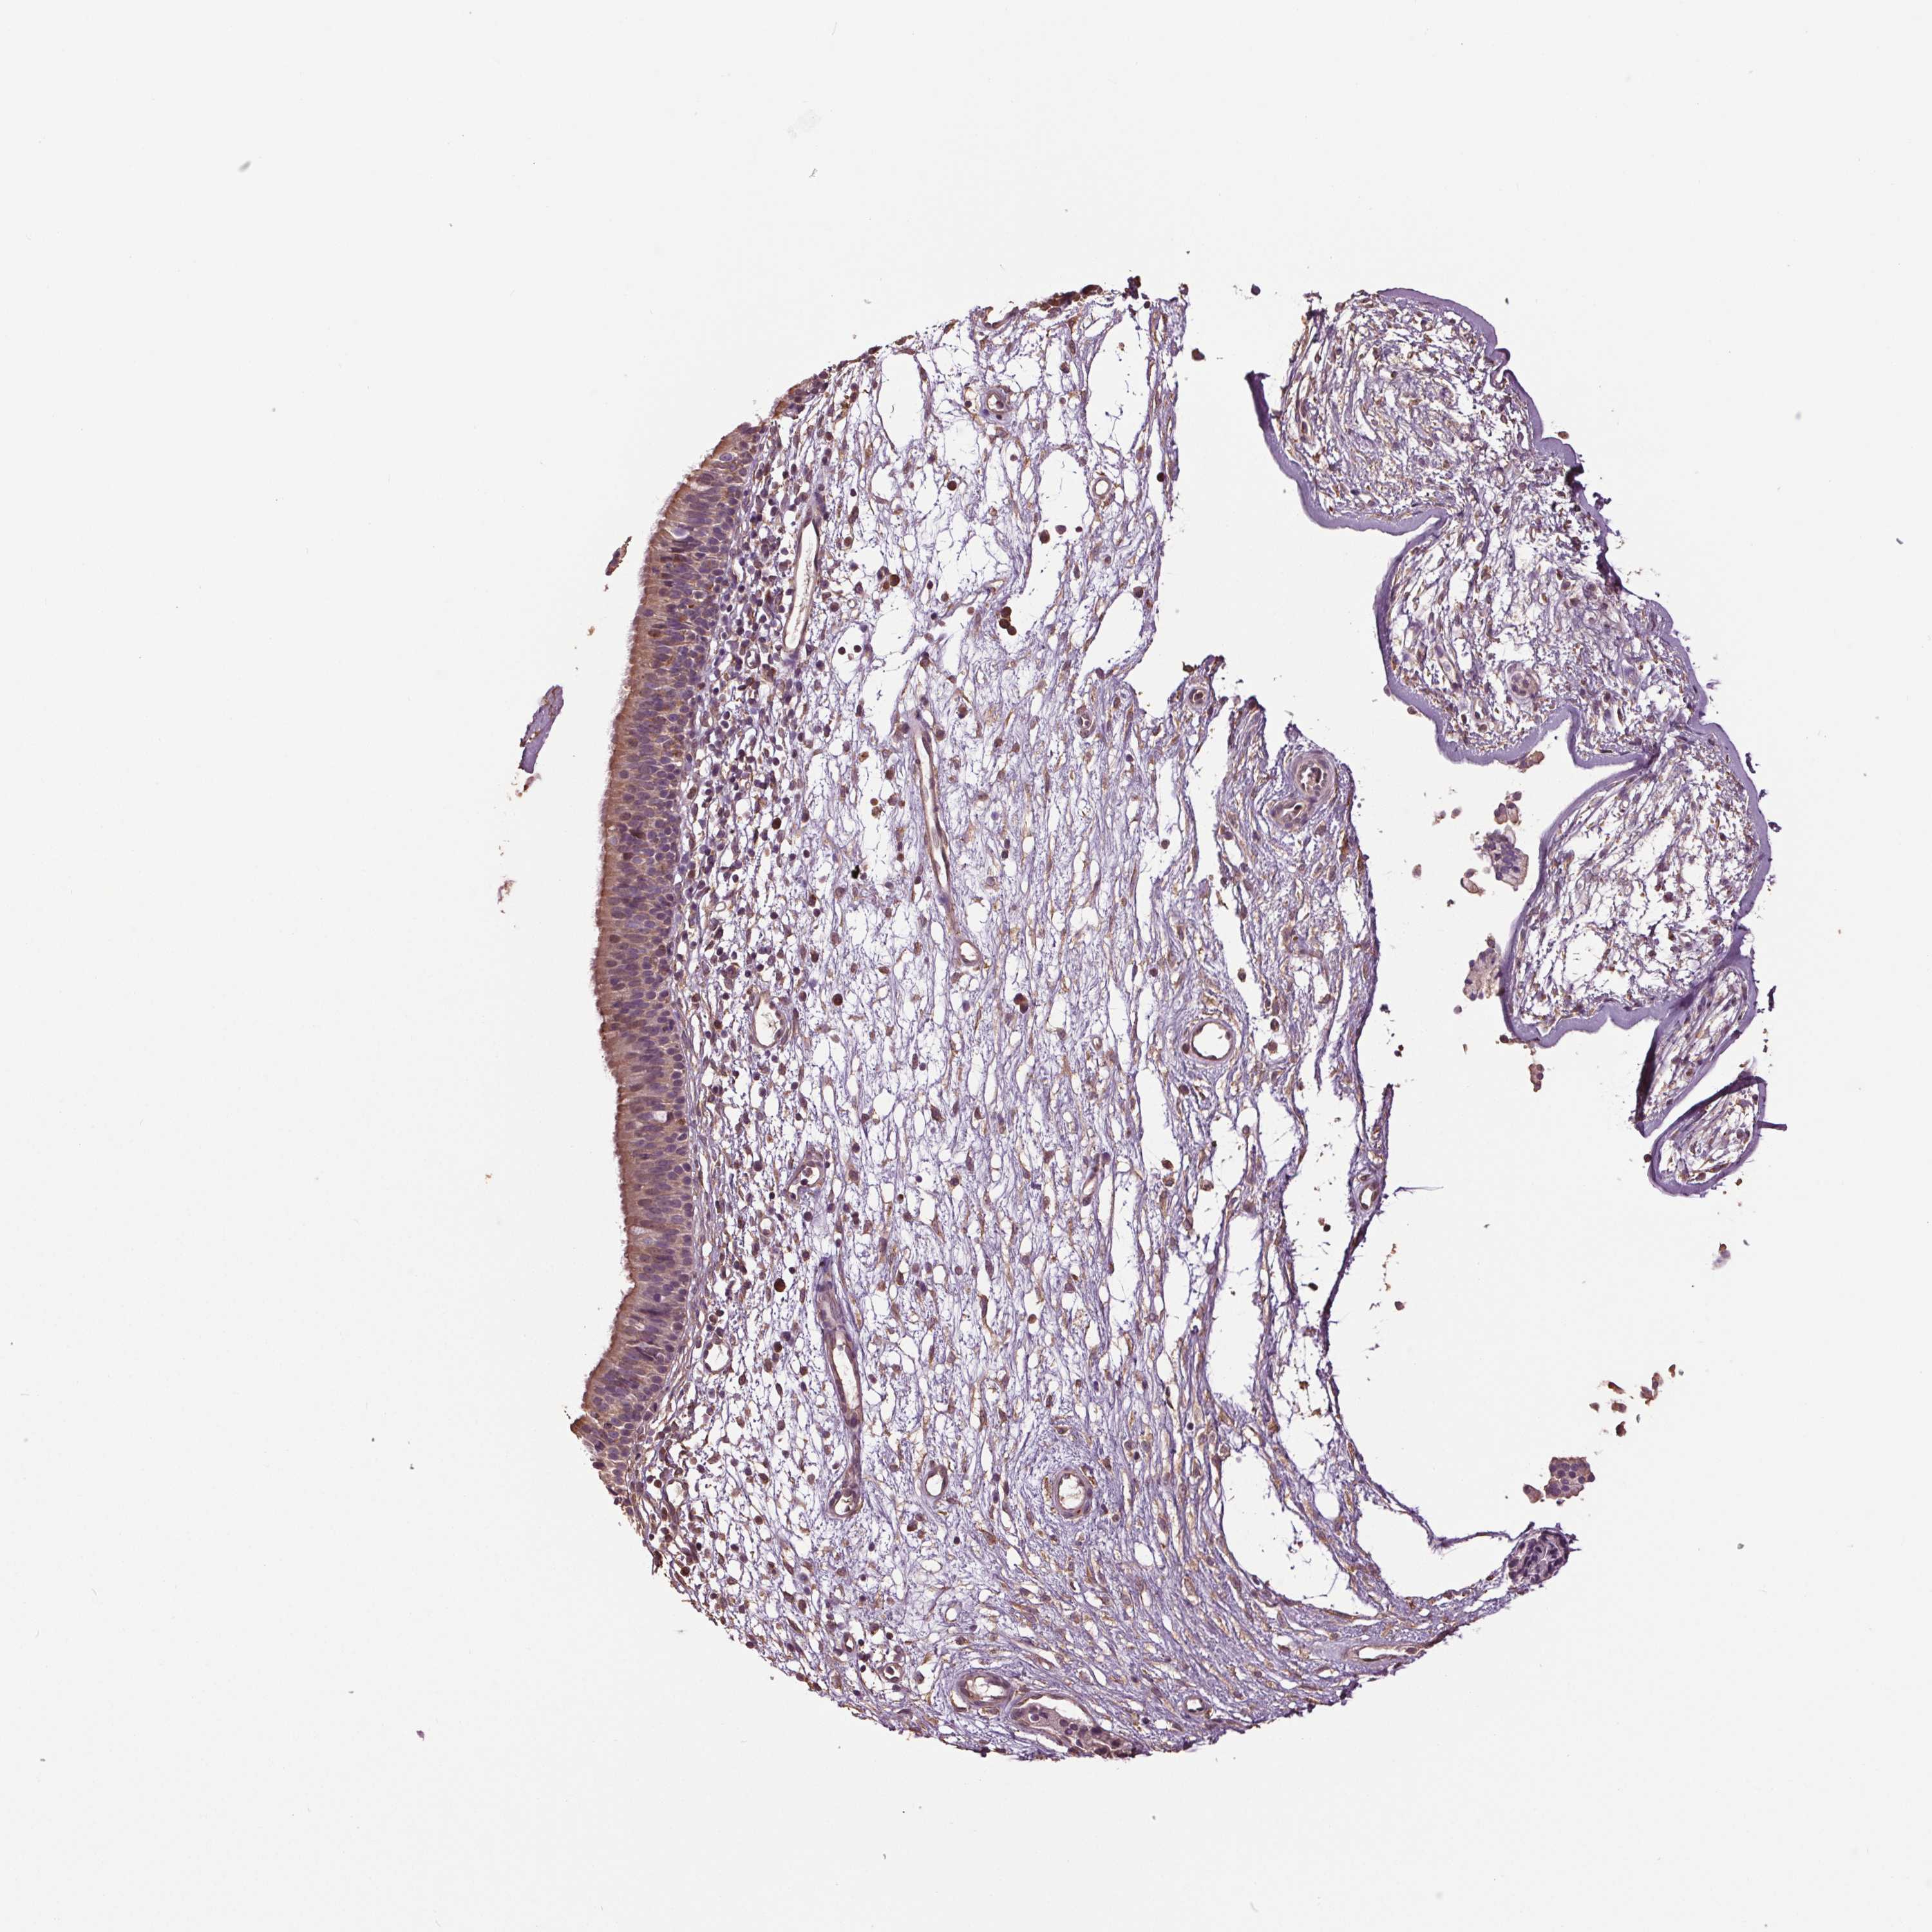

RNPEP